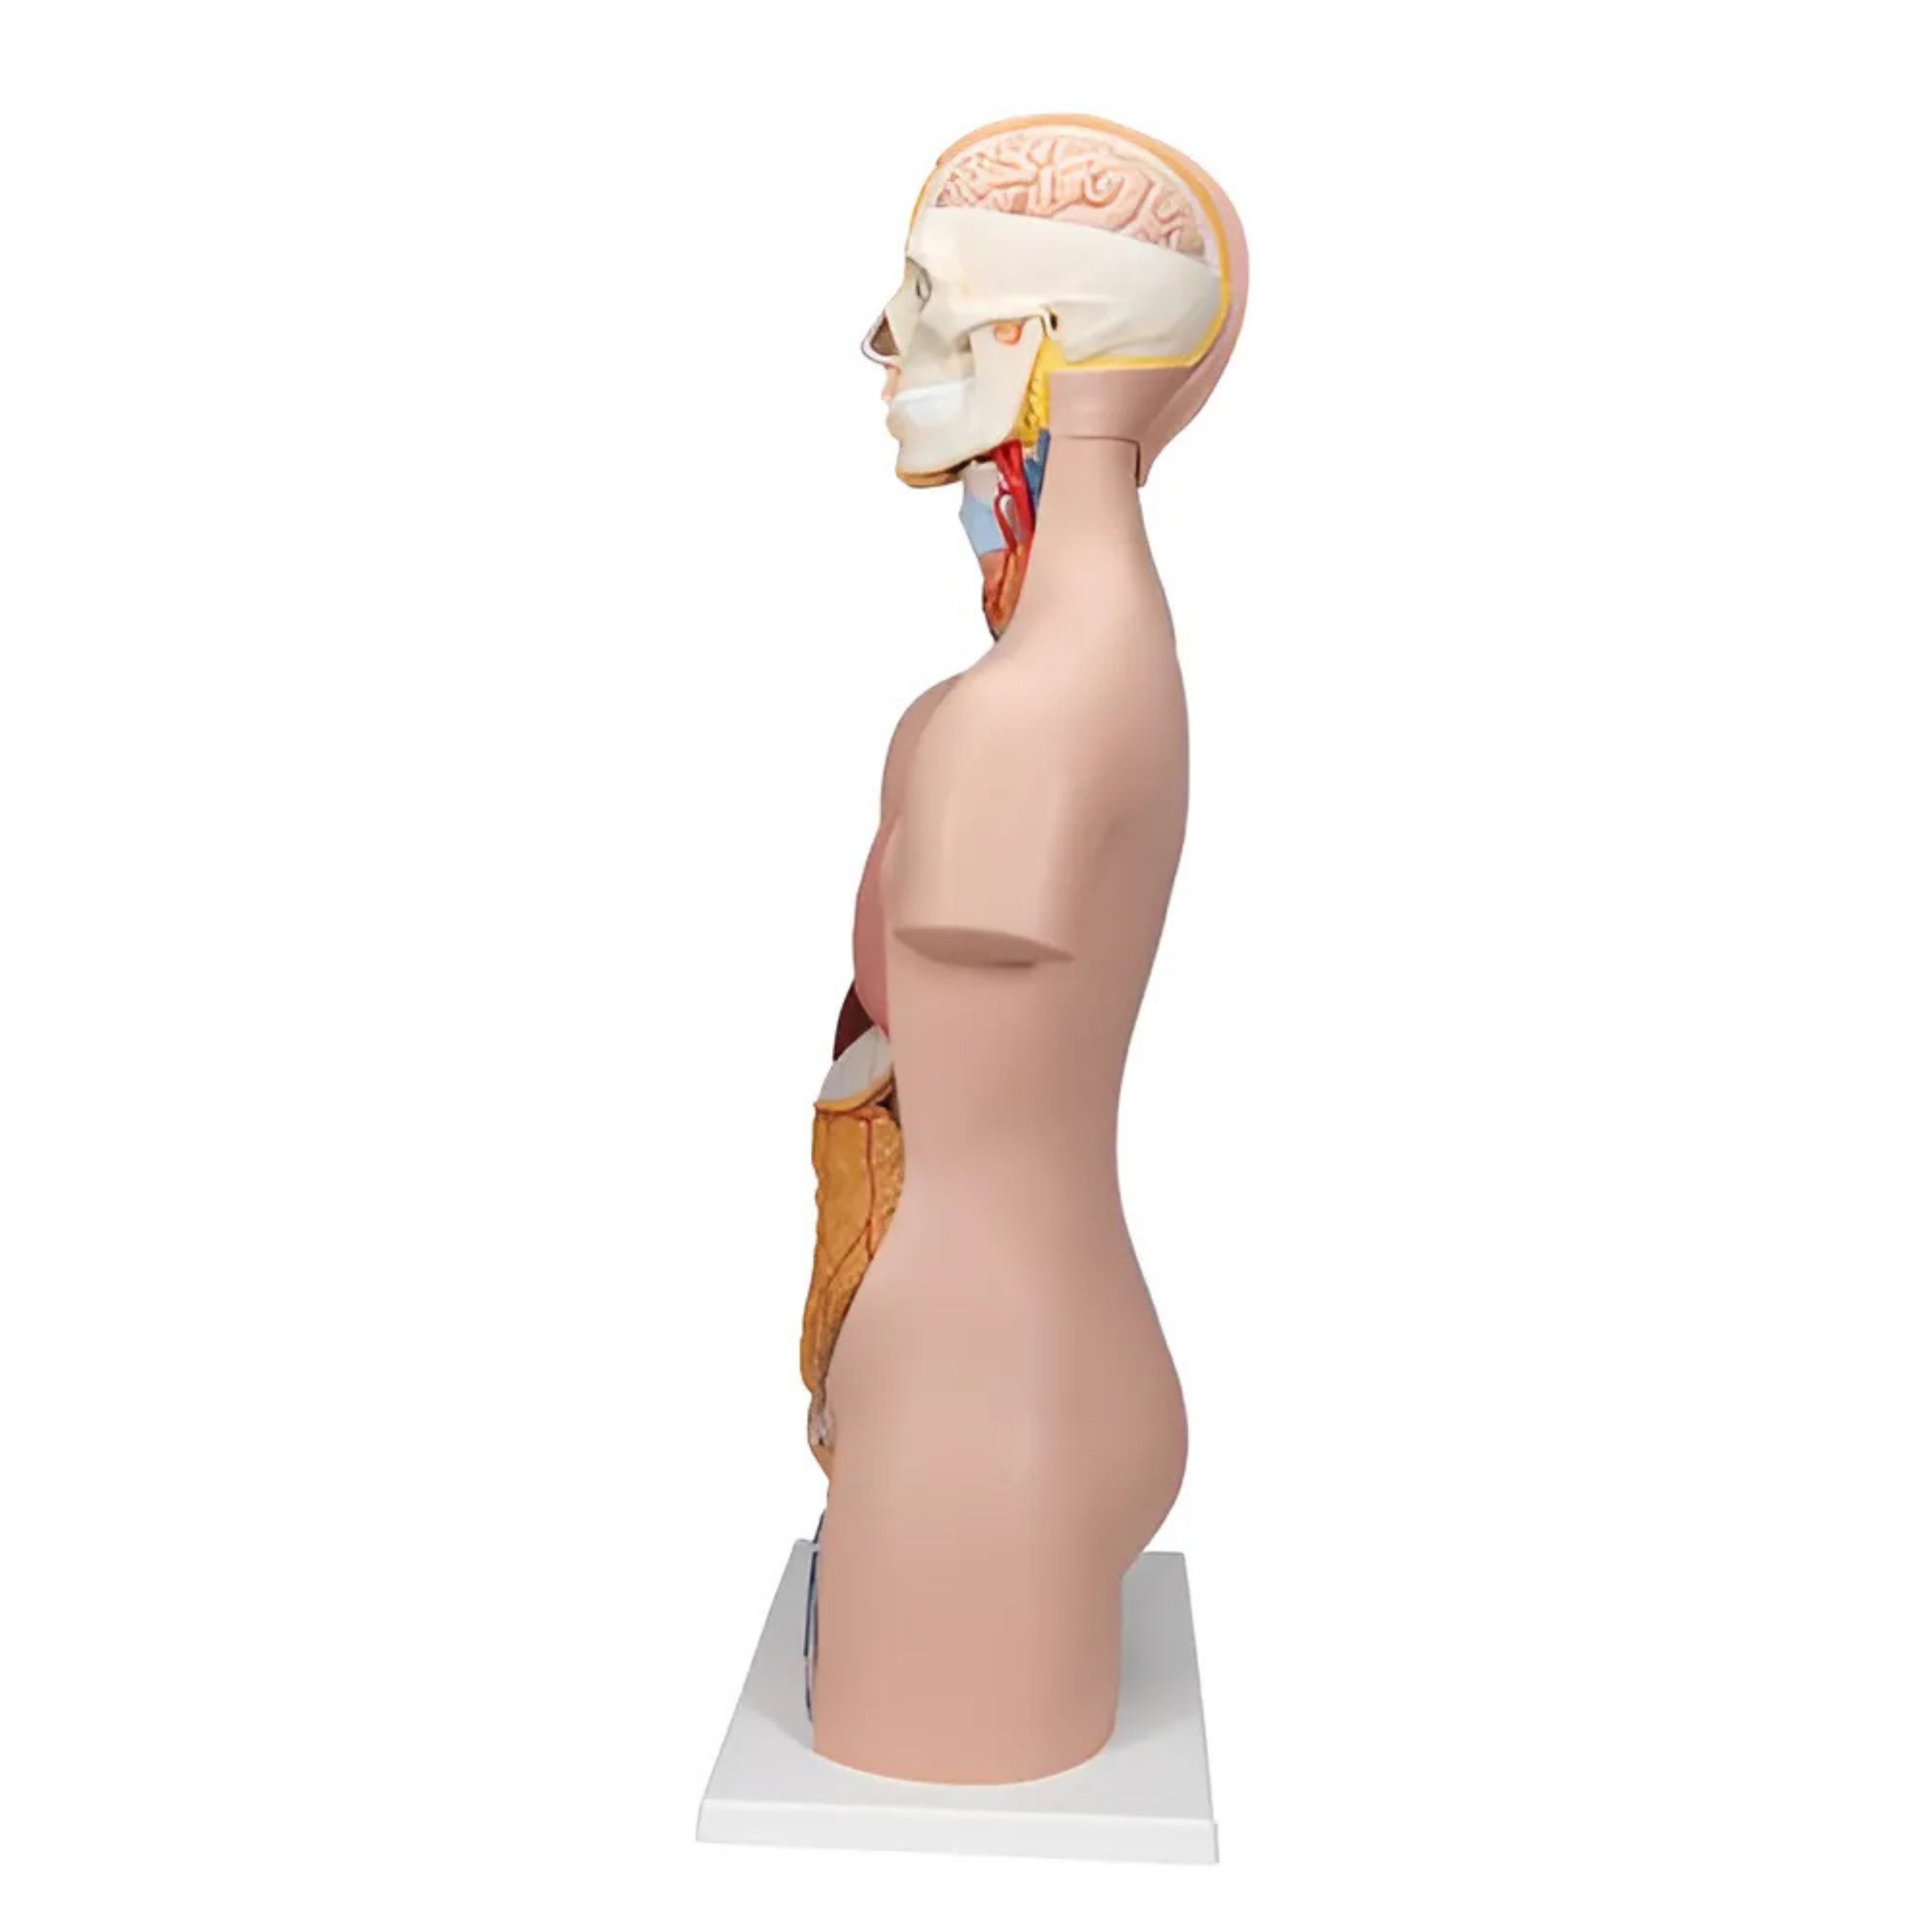

Torso clásico con espalda abierta, 18 partes - 3B Smart Anatomy

Precio de venta$33,762.96